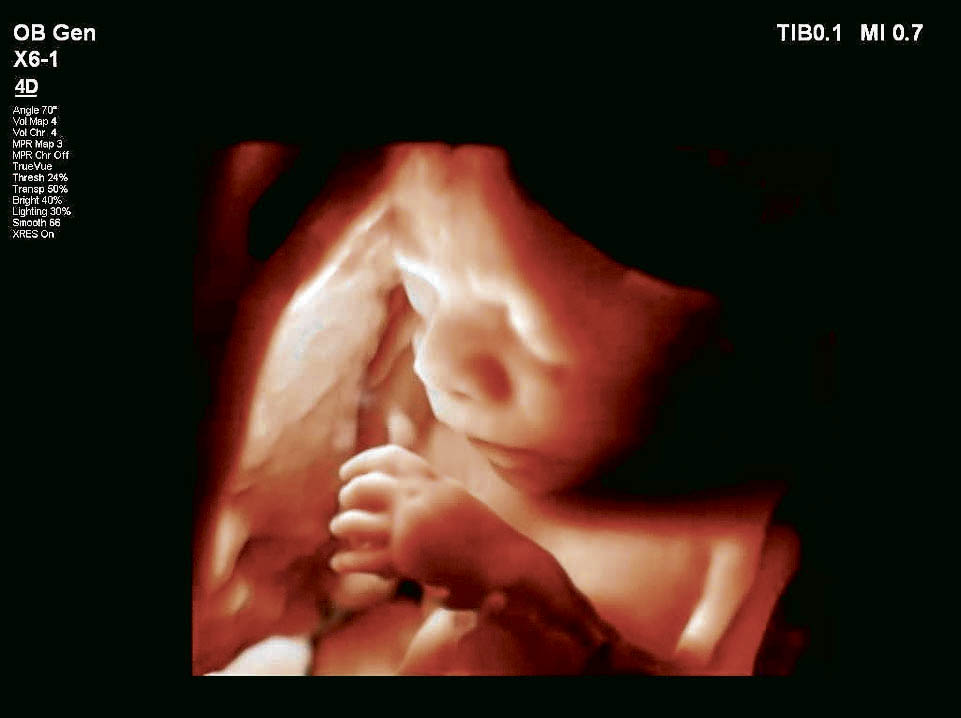

Grávida participa de teste ao examinar bebê no aparelho de ultrassom Crédito: Hucam/Divulgação

Mais do que uma imagem de ultrassom comum, a máquina nova permite visualizar o feto em três dimensões em movimento. “O aparelho tem uma definição muito refinada e consegue produzir imagens em três dimensões, visualizando lesões de um tamanho que nenhum outro equipamento pode fazer”, explicou o médico.

Imagem da máquina nova: é possível ver o feto com detalhes em três dimensões Crédito: Hucam/Divulgação